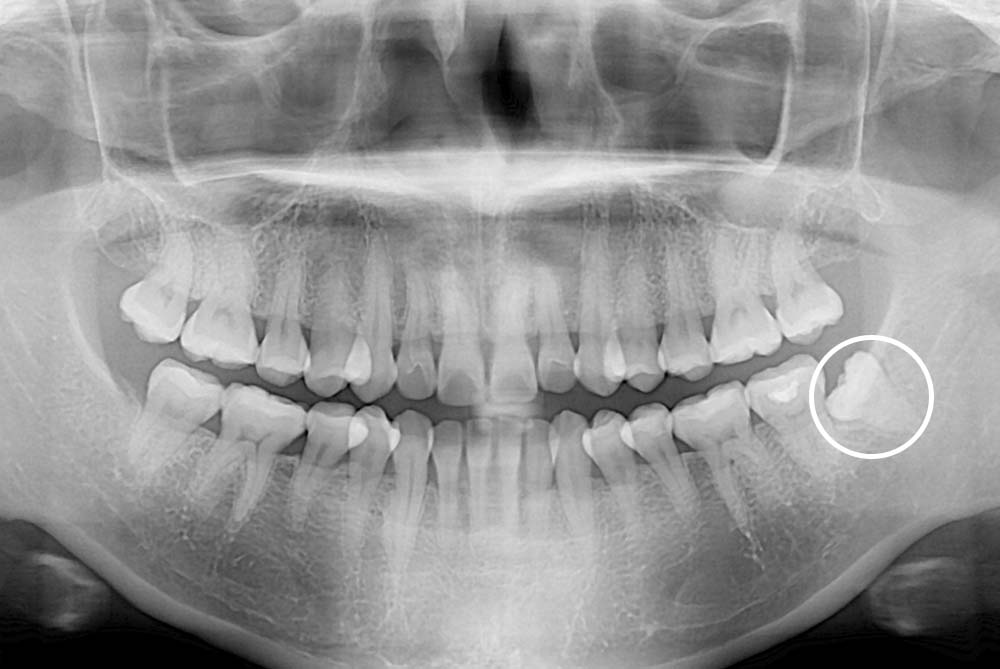

[사랑니] 매복 사랑니 발치

치료전 : 2019-04-24